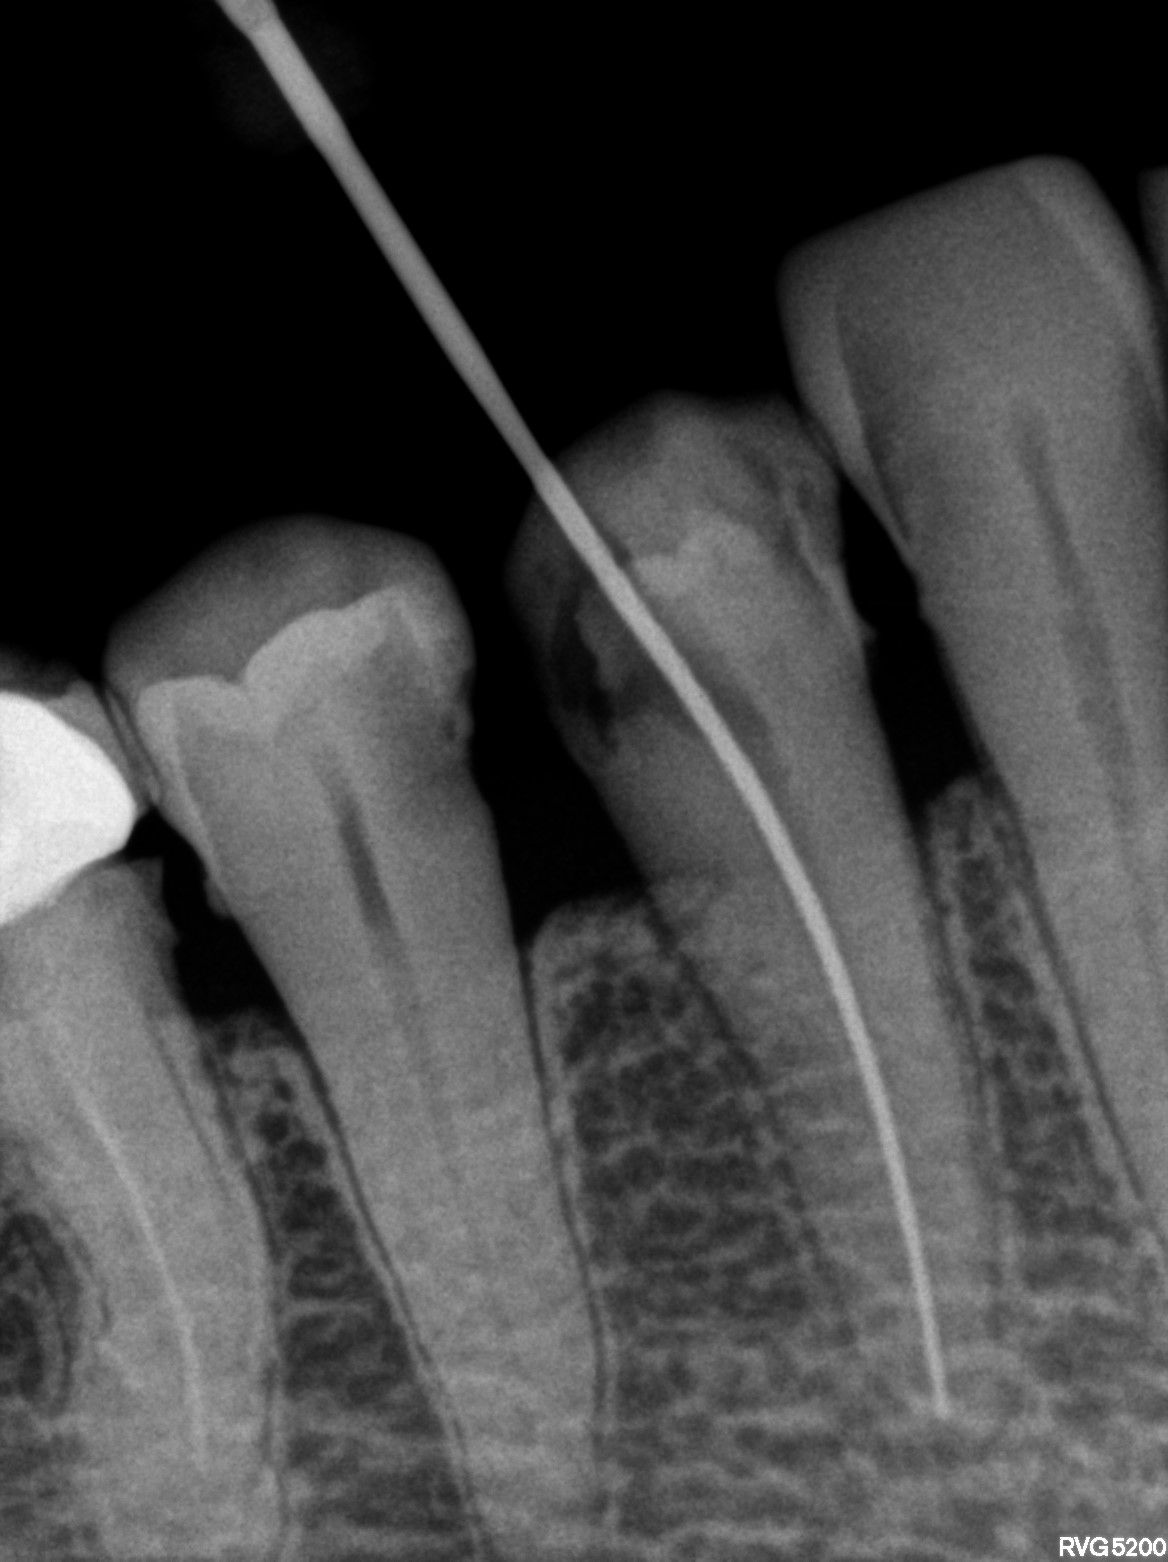

Dental Radiographs FHIR: DocumentReference · LOINC 24641-7

R61.jpg

24641-7